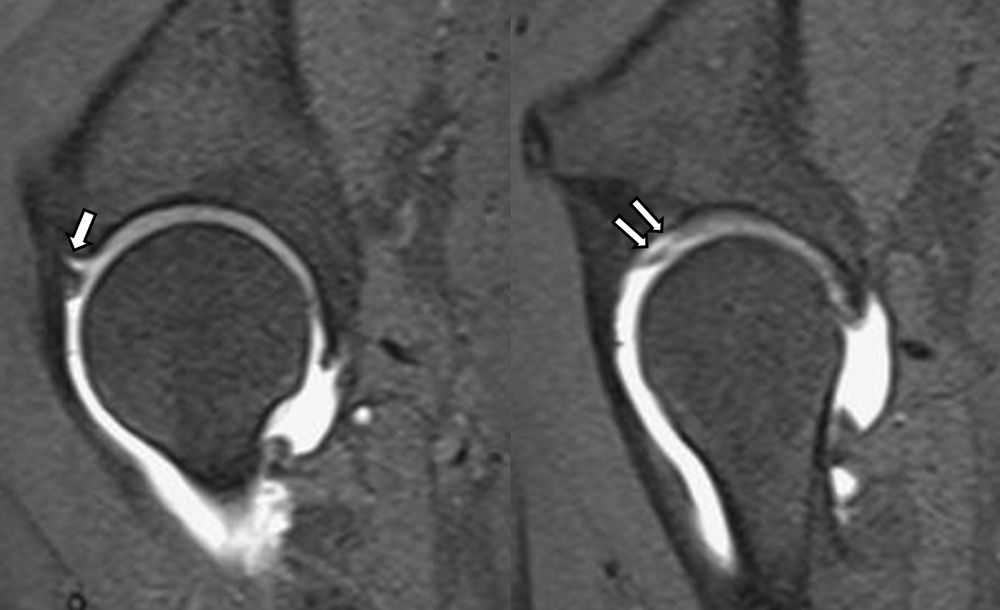

Είναι μια ελάχιστα επεμβατική απεικονιστική μέθοδος που επιτρέπει τη λεπτομερέστερη διερεύνηση του εσωτερικού των αρθρώσεων. Η ασφαλής έγχυση σκιαγραφικού εντός της άρθρωσης υπό ακτινολογική καθοδήγηση και η ακόλουθη απεικόνιση της άρθρωσης με αξονική ή μαγνητική τομογραφία (ή και με συνδυασμό των μεθόδων) αποσαφηνίζει βλάβες του χόνδρου και κακώσεις-ρήξεις συνδέσμων και τενόντων με υψηλή ακρίβεια, συμβάλλοντας σημαντικά στο λεπτομερή χειρουργικό σχεδιασμό.